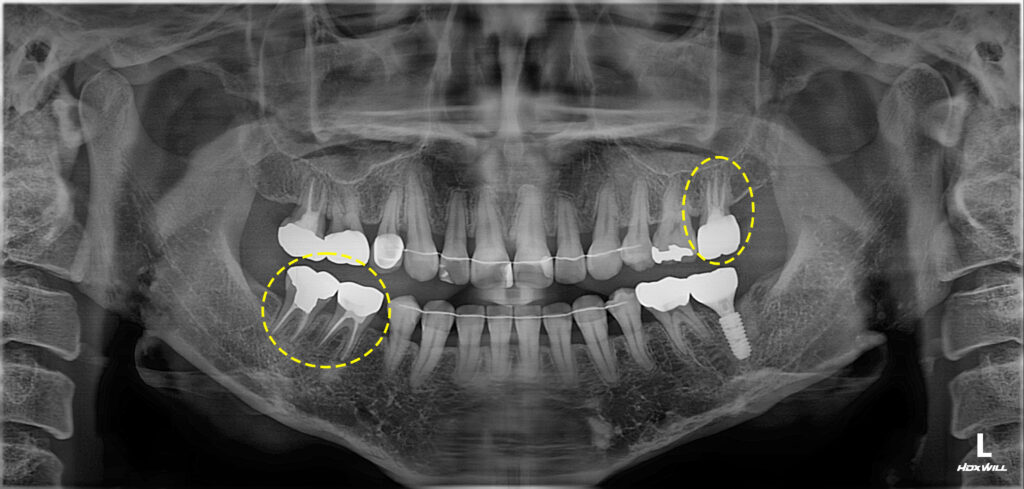

임신 중에도 안정적으로 치료가 가능한

중기에 치료를 결정하여 기존 크라운을

교체 완료 하였습니다.

다시 재충전후 보철을 진행하여 현재까지

통증 없이 현재까지 잘 유지하고 계십니다.

왼쪽 아래 임플란트까지 모든 치료를

마무리하였는데요.